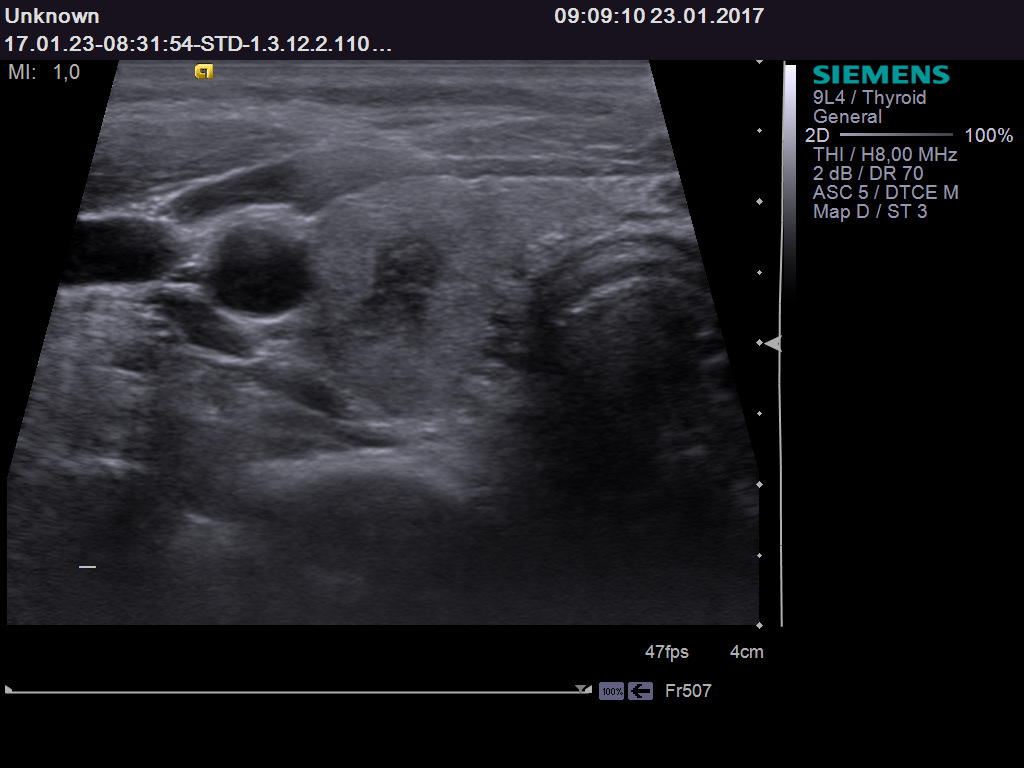

TI-RADS 2. Очаговые образования, не требующие морфологической оценки (макрофолликулы; губчатые или кистозные узлы), представленные на рис. 1.

Рис. 1. Категория TI-RADS 2: а – кистозно расширенный или макрофолликул; б – губчатый узел (стрелки).